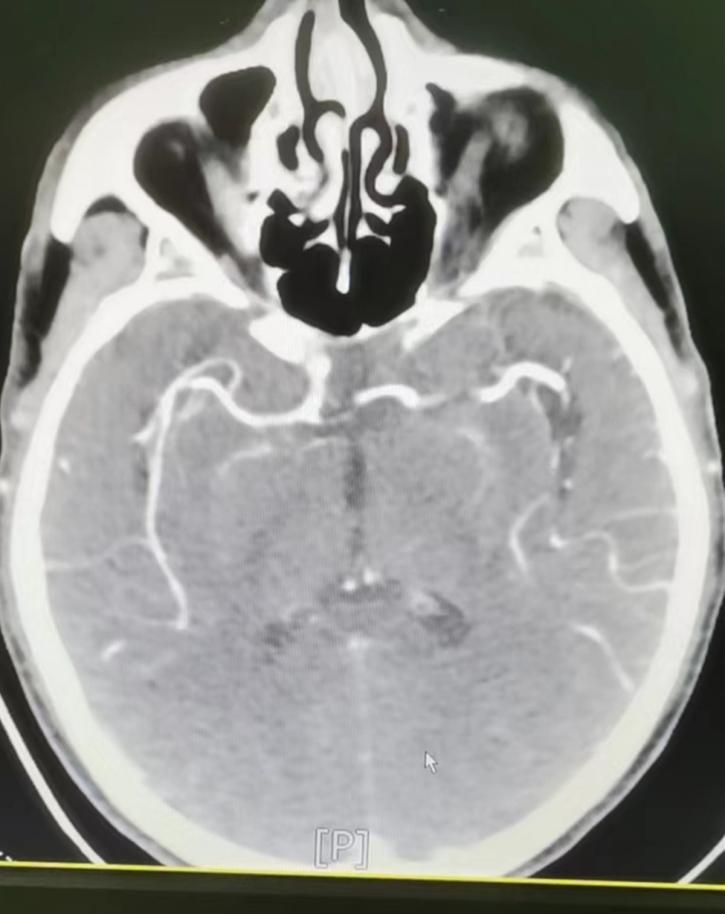

8月28日,商洛市管控区一名66岁男性突发右侧肢体无力,当地评估可能需要介入治疗,遂急诊转入我院。神经内科急诊介入团队第一时间响应,协助发热单元和影像科进行大血管CTA评估。鉴于患者大血管通畅,无急诊神经介入指征,遂制定了双联抗血小板治疗方案,并在感控部门评估后及时转入神经内科病房。目前患者肢体无力恢复正常,顺利出院。

图2 CTA显示大血管通畅